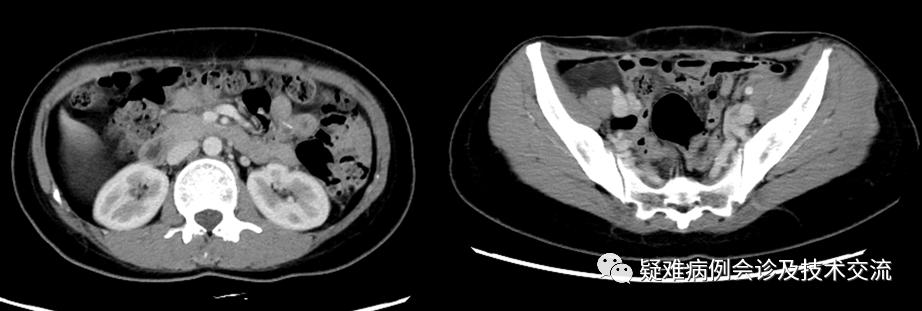

本例患者CT提示肿瘤上下界:

本例患者术前动态CT: